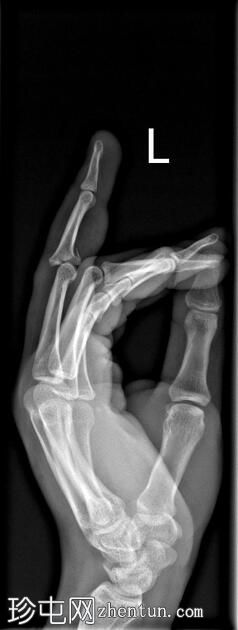

斜位

侧位

可见第三指中节指骨基底部轻微移位骨折,延伸至近端指间关节(PIP关节),并伴有软组织肿胀。

第三指中节指骨基底部轻微移位骨折,延伸至近端指间关节(PIP关节)指骨,并伴有软组织肿胀。